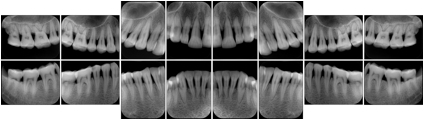

In most standard cases, images are oriented in structured layouts. These structured displays are useful to be shared between providers for reference purposes.

Table OO.1.1-1 shows structured display standard templates, where Viewset ID is based on the Japanese Society for Oral and Maxillofacial Radiology (JSOMR) classification provided by JIRA (Japan Medical Imaging and Radiological Systems Industries Association, www.jira-net.or.jp). Expected or typical teeth to be imaged location, region and designation codes are based on ISO 3950-2010, Dentistry - Designation system for teeth and areas of the oral cavity. For all the hanging protocols listed in OO.1.1-1, the value to use for Hanging Protocol Creator (0072,0008) is "JSOMR" and the value to use for Hanging Protocol Name (0072,0002) does not include "JSOMR" (e.g., "DL-S001A", not "JSOMR DL-S001A").